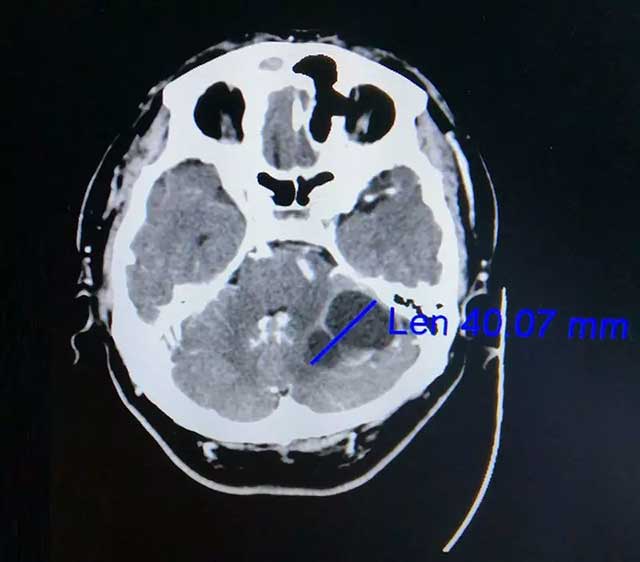

在家人陪伴下,劭阿伯到医院做了检查。查头颅CT提示:左侧小脑囊实性占位,很可能是转移瘤。后又经PET-CT检查提示:左侧小脑半球不规则囊性占位,转移可能性大,原发肿瘤待排。此时悬在劭阿伯心中的“达摩克利斯之剑”摇摇欲坠,原来两年前劭阿伯曾患肺癌,接受过放化疗。为寻求进一步治疗,劭阿伯一家慕名来到上海蓝十字脑科医院。

▲ 增强CT显示肿瘤达4公分大小

在查体时,劭阿伯双侧指鼻试验略迟缓、欠稳定,双侧跟膝胫实验略欠稳定,闭目难立征不合作。一般来说,指鼻动作笨拙、不准确、不协调、不平稳说明病侧上肢共济失调,提示小脑半球的病变。患者有明确肺癌病史,根据影像学表现考虑为:肺癌左侧小脑转移。